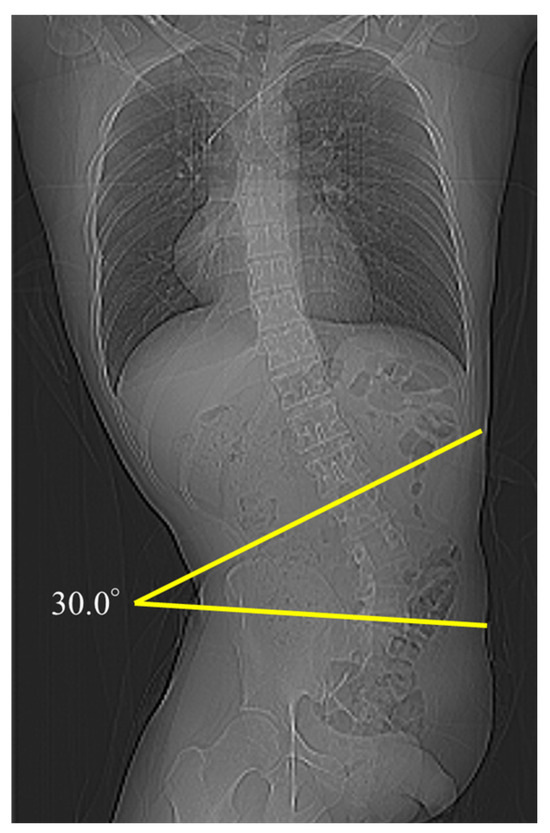

2.2. Parameter Measurements